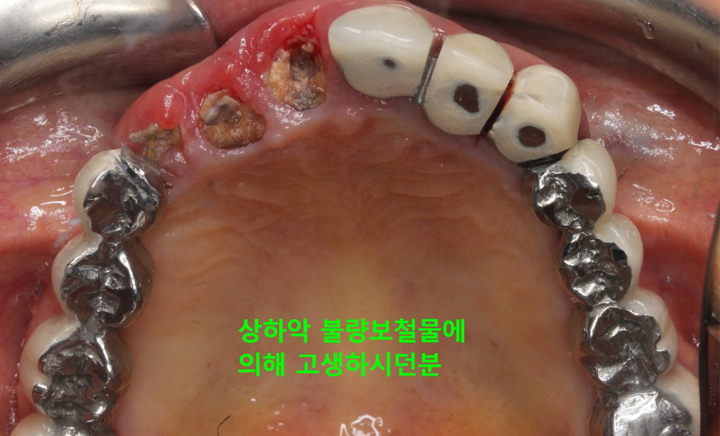

CASE #1